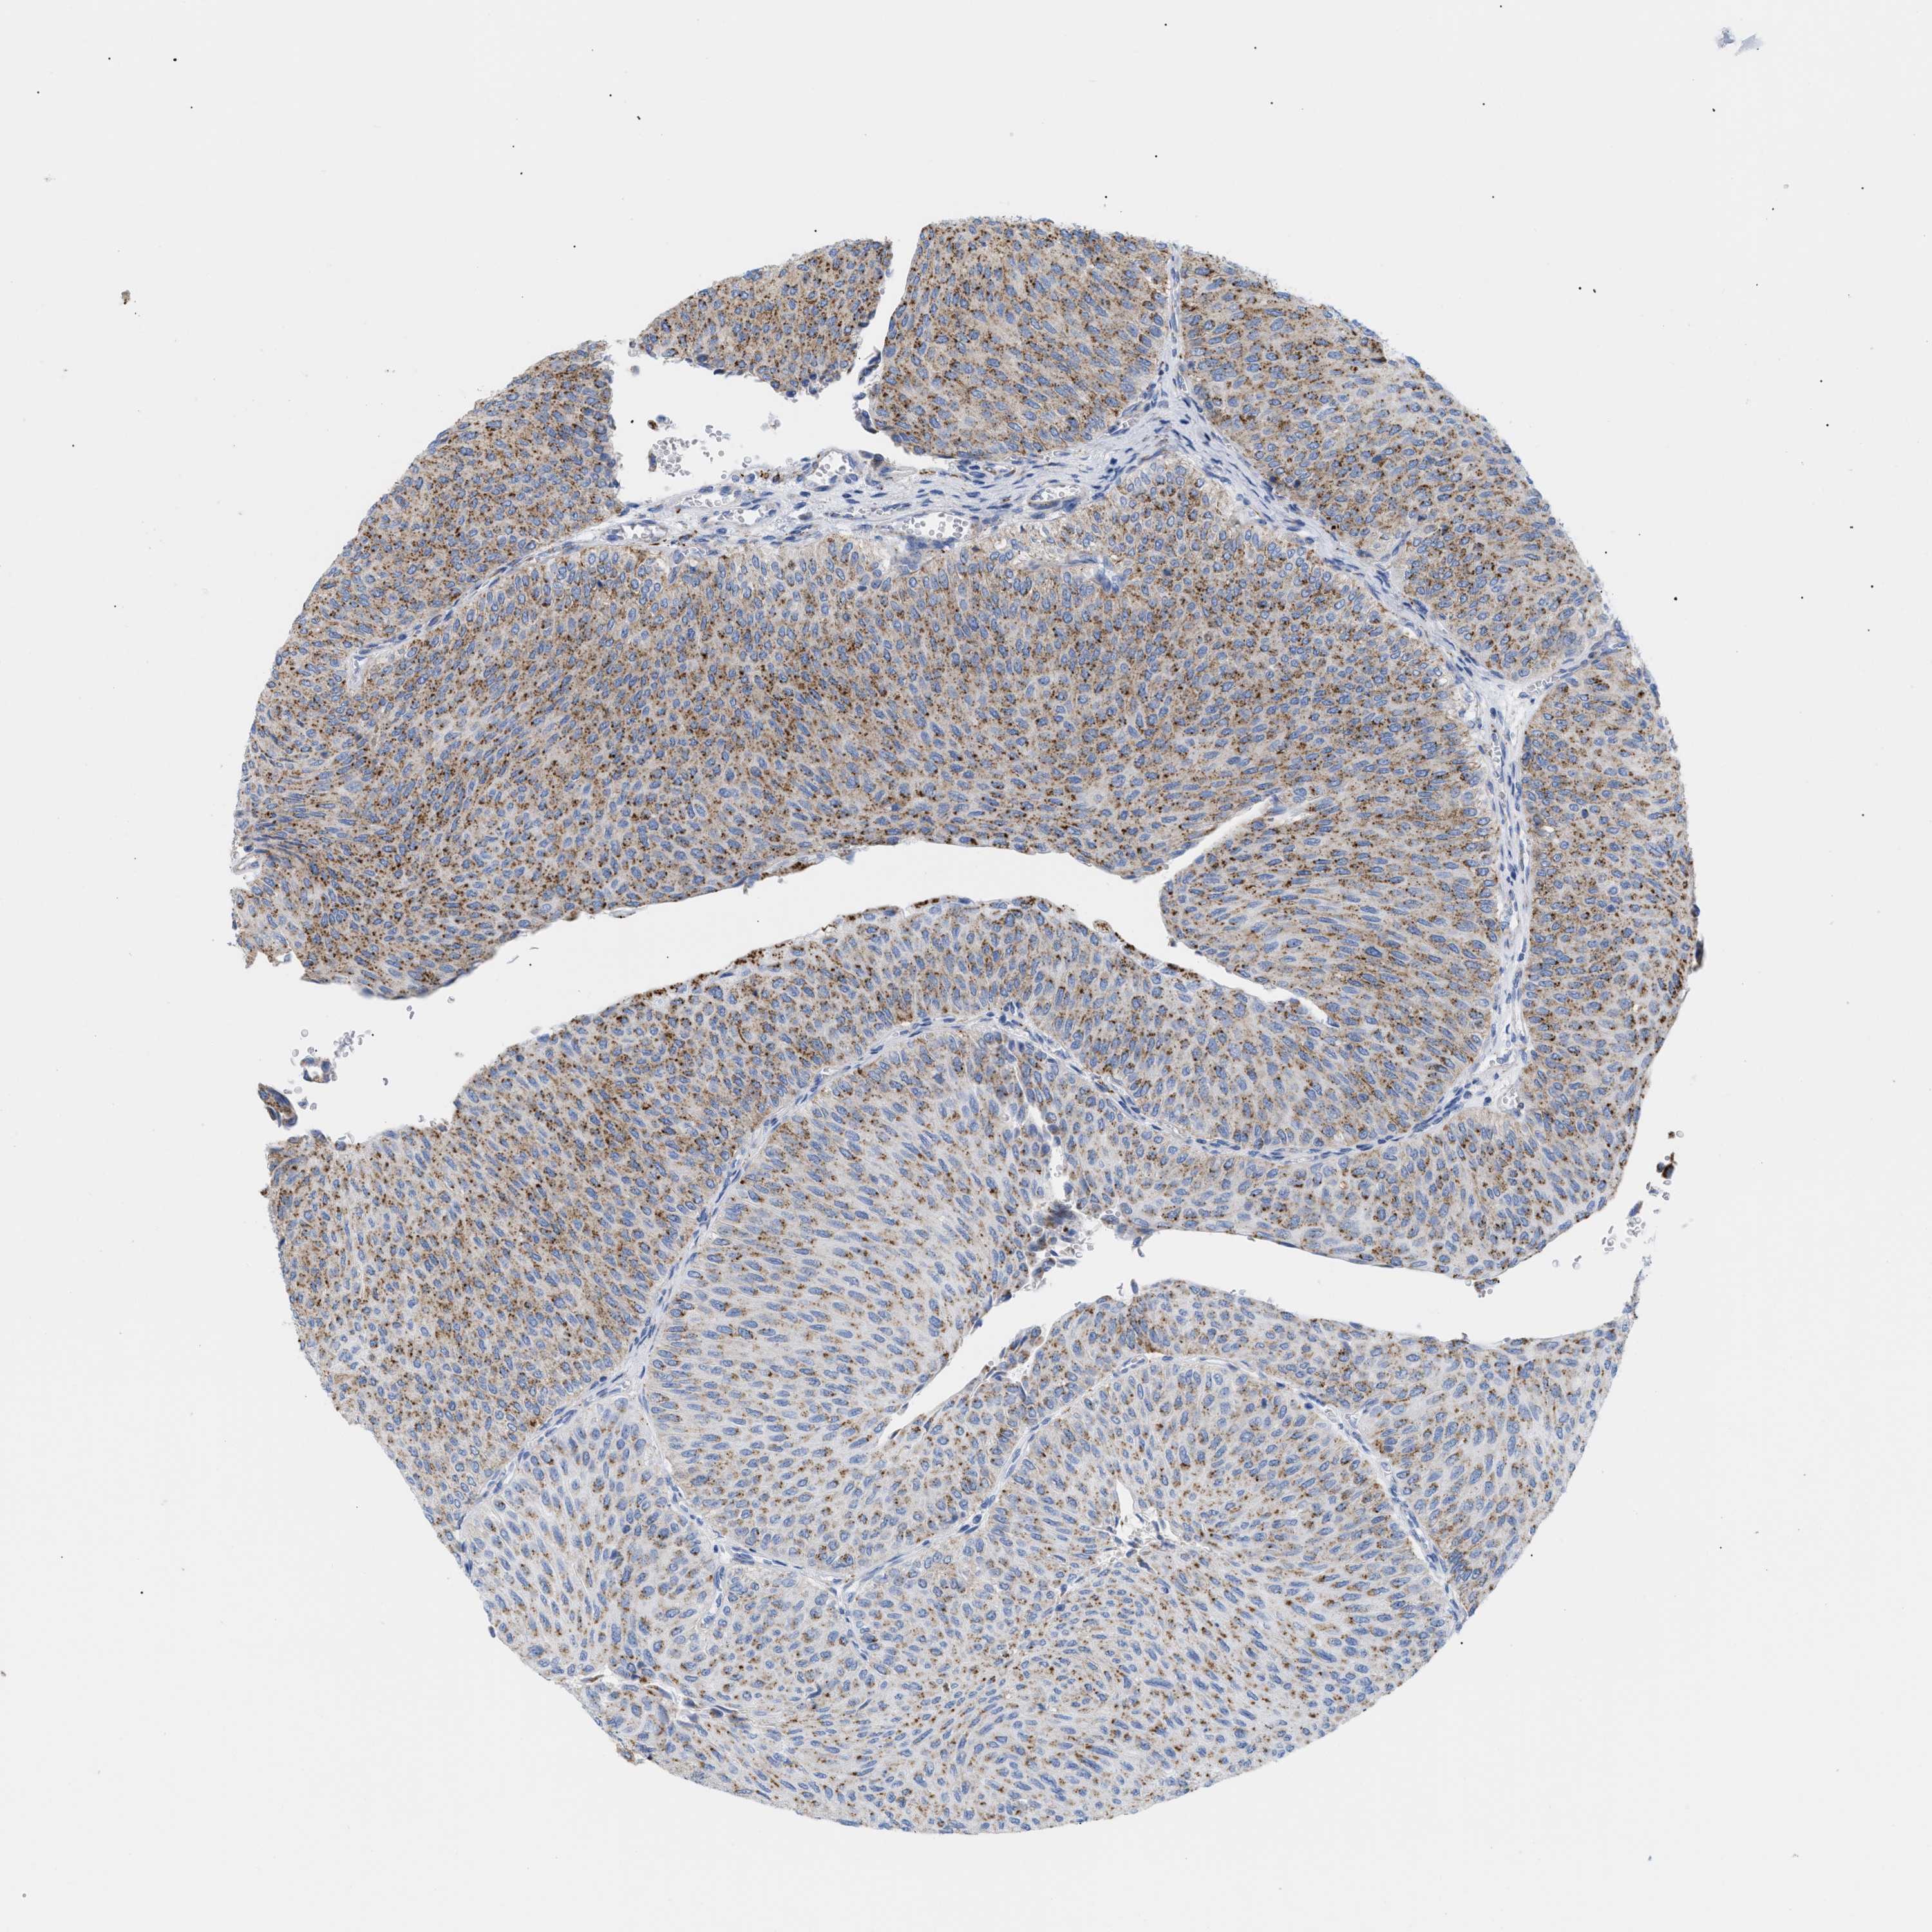

UROTHELIAL CANCER - Protein expressioni

A mouse-over function shows sample information and annotation data. Click on an image to view it in a full screen mode. Samples can be filtered based on level of antibody staining by selecting one or several of the following categories: high, medium, low and not detected. The assay and annotation is described here.

Antibody stainingi

Antibody staining in the annotated cell types in the current human tissue is reported as not detected, low, medium, or high, based on conventional immunohistochemistry profiling in selected tissues. This score is based on the combination of the staining intensity and fraction of stained cells.

Each image is clickable and will lead to virtual microscopy that enables deeper exploration of all samples and also displays staining intensity scores, fraction scores and subcellular localization as well as patient and tissue information for each sample.

Antibody HPA018036

Antibody HPA061701

Staining

High

Medium

Low

Not detected

Intensity

Strong

Moderate

Weak

Negative

Quantity

>75%

75%-25%

<25%

None

Location

Nuclear

Cytoplasmic/membranous

Cytoplasmic/membranous,nuclear

Urothelial carcinoma, Low grade

Urothelial carcinoma, High grade

Urothelial carcinoma, NOS